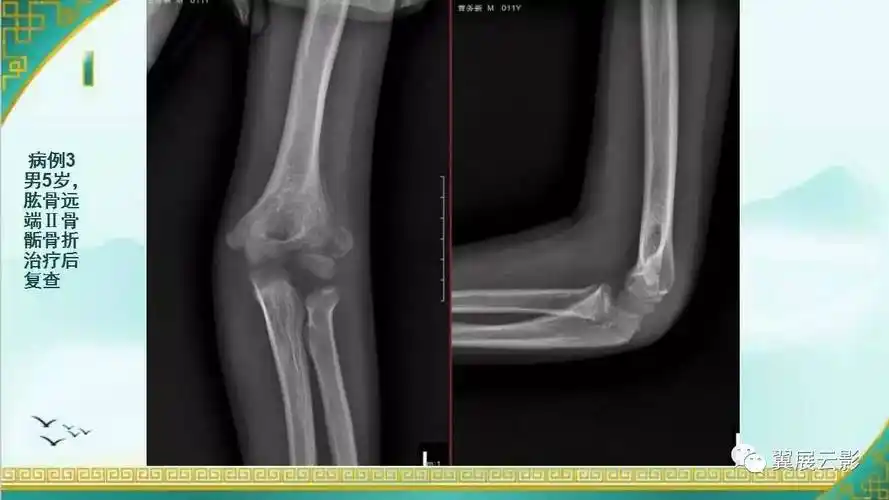

儿童肘关节损伤x线诊断

儿童肘关节骨折的x线表现

影像基础儿童肘关节损伤x线诊断

儿童肘关节骨骺损伤诊疗概要